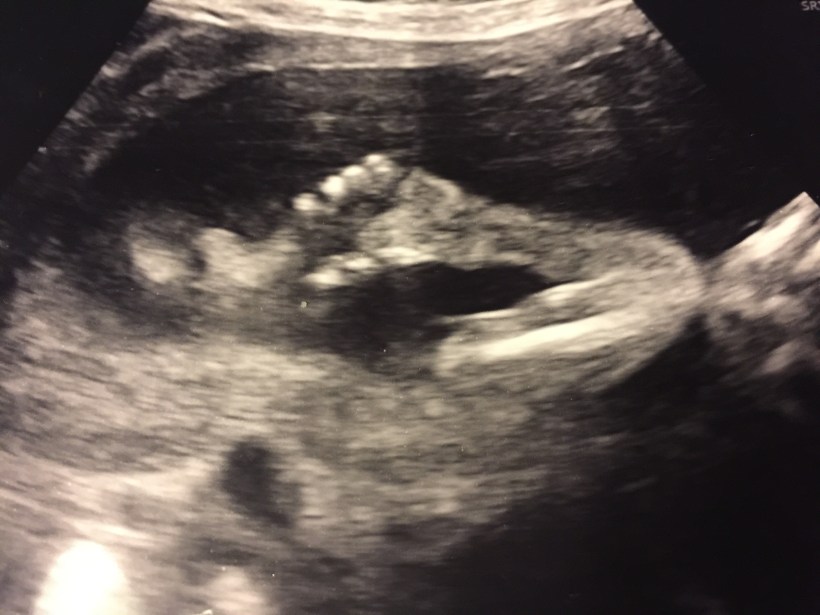

Käänne tapahtui raskausviikolla 20. Alkuraskaus oli sujunut tavanomaisesti. Menin rakenneultraan Kätilöopistolle suoraan työpalaverista, josta lähtiessäni huikkasin, että ”menemme kuulemaan lapsen sukupuolen.” Odotettu tieto jäi kuitenkin muiden uutisten varjoon.

”Täällä on molemmat kädet ja kymmenen sormea. Ja jalat ja kymmenen varvasta ja kaikki ihan normaalisti, mutta – – -”

Siihen sanaan elämämme pysähtyi. Sikiön niska ja kaula näyttivät normaalia paksummilta. Kätilö kutsui kollegansa tutkimaan ultraäänikuvaa, ja sitten lääkärin. Tässä vaiheessa varmaan jo itkin, ja puolisoni istui hiljaa vieressäni kädestäni pidellen. Saimme seuraavalle päivälle kiireellisen ajan Naistenklinikan Sikiötutkimusyksikköön.

ultraääni